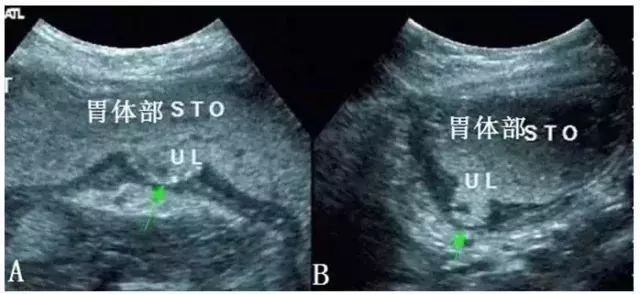

图7 胃角巨大型溃疡(UL示溃疡灶)

图10 胃角胃小弯多发型溃疡(UL示溃疡灶)